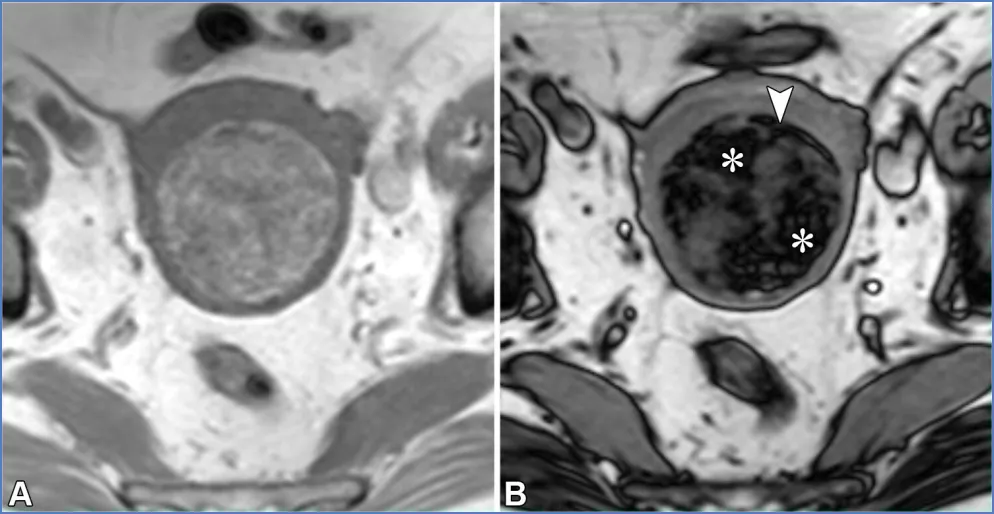

对于卵巢来源的病变,子宫内膜异位囊肿和出血性囊肿是可能的诊断。子宫内膜异位囊肿是子宫内膜异位症的常见表现,子宫内膜异位症影响10%的育龄女性,并与慢性疼痛和不孕相关(10)。子宫内膜异位症的特征是子宫内膜腺体和间质出现在子宫内膜外,导致炎症、纤维化和结构扭曲。影像学检查可能会发现子宫内膜异位囊肿和深部子宫内膜异位症。子宫内膜异位囊肿表现为卵巢囊肿,通常为多灶性和双侧性,由于周期性出血,在T1加权像上呈弥漫性显著高信号,在T2加权像上呈阴影(变暗)改变(图21)。由纤维化和含铁血黄素形成的厚T2低信号 rim、由血块形成的T2低信号斑点以及病变长期存在,均会提高子宫内膜异位囊肿诊断的特异性(65,66)。

图21. 一位20岁痛经女性患者的双侧子宫内膜异位囊肿。(A、B)轴位脂肪抑制T1加权像(A)和T2加权像(B)显示了子宫内膜异位囊肿的典型特征,如双侧T1高信号病灶(A中的*)伴T2信号衰减(B中的*)、T2低信号囊壁以及病灶内T2低信号斑点(B中的箭头),所有这些均提示慢性反复出血。(C)对比增强脂肪抑制T1加权减影图像证实无强化的实性组织。